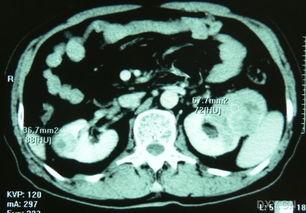

拿到双肾B超视频后,接下来就是解读环节了。医生会根据视频中的图像,分析肾脏的大小、形态、位置以及内部结构,从而判断是否存在异常。

一般来说,双肾B超视频会关注以下几个方面:

1. 肾脏大小:肾脏的大小与年龄、性别等因素有关。如果肾脏大小异常,可能是肾脏疾病的表现。

2. 肾脏形态:肾脏的形态应该是光滑、对称的。如果出现肿块、囊肿等异常,就需要进一步检查。

3. 肾脏位置:肾脏的位置应该在腰部两侧,如果位置异常,可能是肾脏下垂等疾病的表现。

4. 内部结构:肾脏内部结构包括肾皮质、肾髓质等。如果出现异常,可能是肾脏疾病的表现。